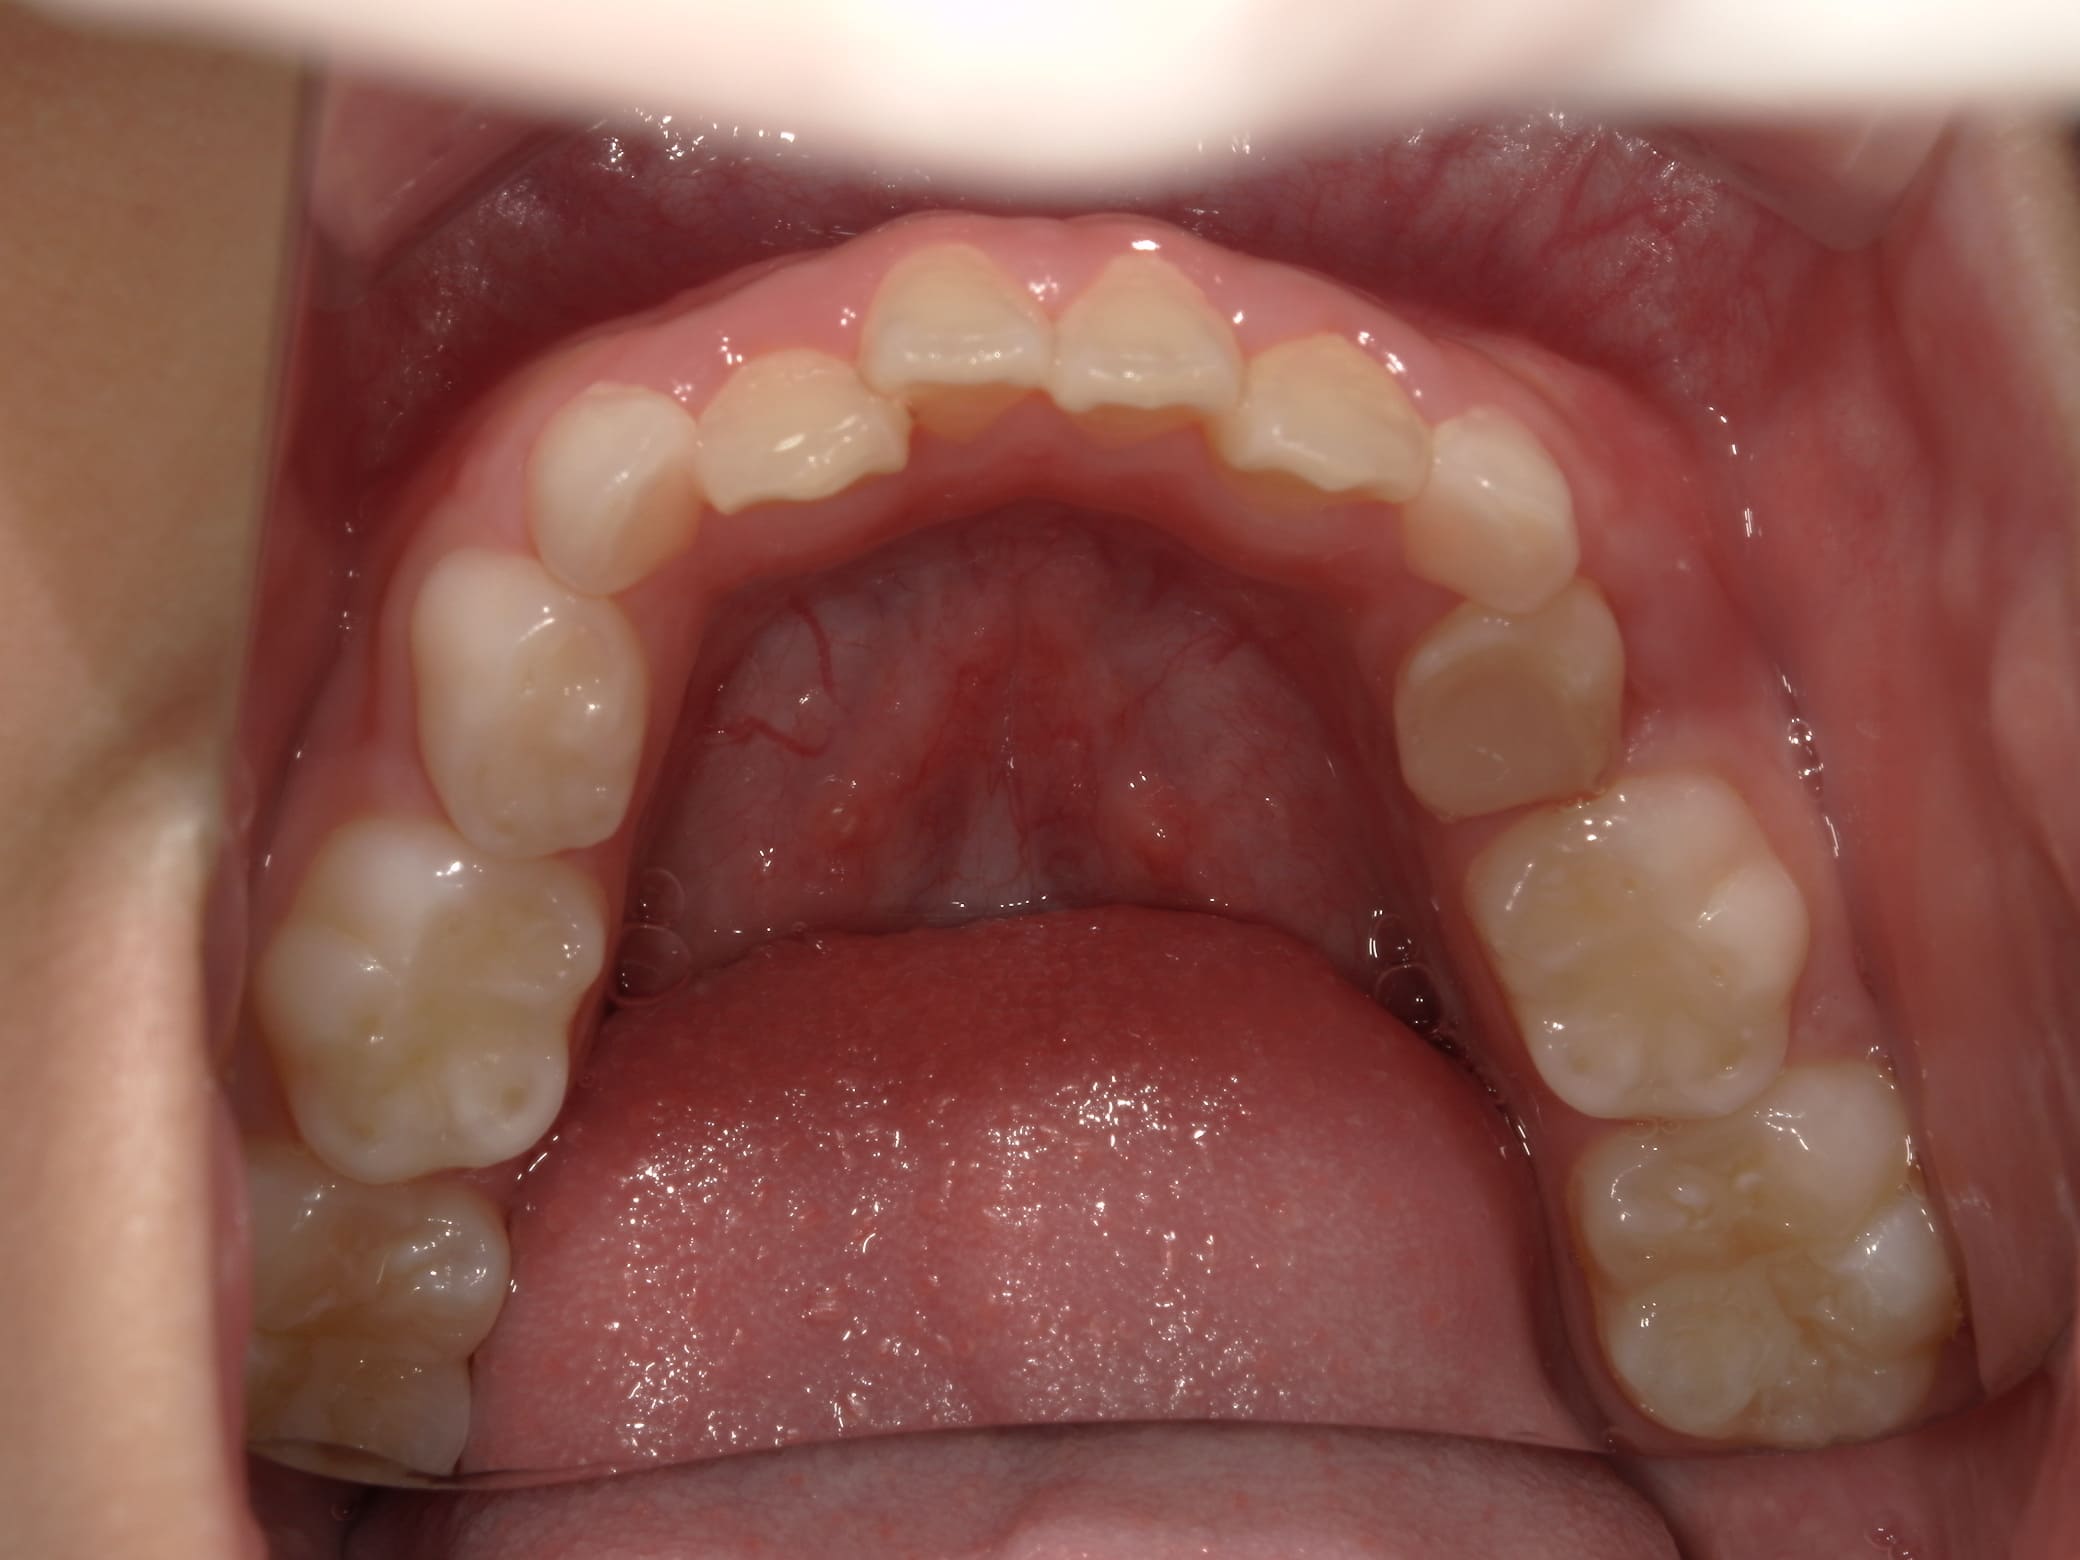

| 年齢・性別 | 7歳1ヶ月の男児 |

|---|---|

| 主訴 | 歯の生えるスペース不足が懸念され、歯列の乱れ(叢生)を整えるために来院された患者様です。 |

| 治療期間・回数 | 1年3ヶ月・11回 |

| 費用 | 420,000円(税別) |